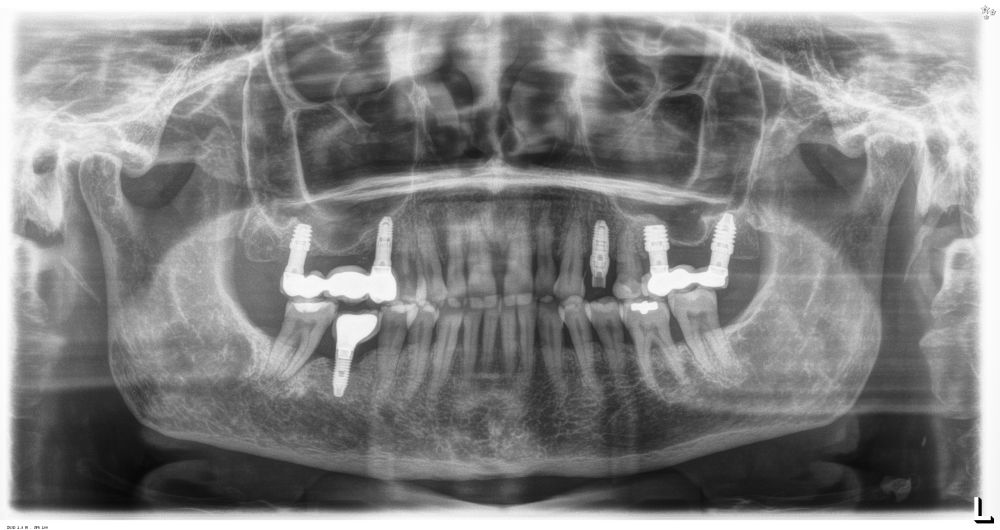

Todas las cirugías fueron realizadas por un único cirujano bajo anestesia local, tras un diagnóstico previo del lecho óseo mediante tomografía volumétrica (CBCT) procesada con un software específico de planificación implantológica (BTI-Scan III). La preparación del lecho implantario se llevó a cabo siguiendo la técnica de fresado biológico a bajas revoluciones descrita por Anitua y cols.19.

Los pacientes acudieron cada 6 meses a la realización de radiografías panorámicas y periapicales de control y sobre estas radiografías y se realizaron las mediciones necesarias para comprobar la estabilidad y pérdida ósea crestal de los implantes. Una vez obtenida la radiografía en formato digital fue calibrada mediante un software específico (Sidexis measure y Digora) a través de una longitud conocida en la radiografía como es el implante dental. Una vez introducimos la medida de calibración, el programa informático realizó un cálculo basado en esta medida para eliminar la magnificación, pudiendo realizar mediciones lineales exentas de este error. La pérdida ósea marginal se definió como la distancia entre el hombro del implante y el primer punto de contacto óseo visible sobre su superficie. En estas visitas se realiza además sondaje de los implantes y se anotaron los posibles signos y síntomas de periimplantitis o mucositis (sangrado espontáneo, al sondaje, inflamación o supuración).

En cuanto a la rehabilitación protésica, en todos los casos se utilizó una prótesis atornillada con transepitelial para prótesis unitaria. La supervivencia de las prótesis fue del 100%, sin encontrarse fracaso en ninguna de ellas al igual que los implantes, con un tiempo de seguimiento de tres años. Durante el primer año, en las visitas de control, ninguno de los implantes mostró sangrado al sondaje ni inflamación de los tejidos periimplantarios. La media de la pérdida ósea en este punto fue de 0,32 mm (+/- 0,60) y la media de la pérdida ósea distal de 0,31 (+/- 0,48). A los dos años, no se registraron tampoco signos inflamatorios en ninguno de los implantes y la pérdida ósea mesial del conjunto fue de media de 0,38 mm (+- 0,54) y la distal de 0,64 mm (+/- 0,70). En la última visita a los 3 años, los tejidos periimplantarios siguieron estables, sin signos de inflamación y la media de la pérdida ósea mesial fue de 0,40 mm (+/- 0,53) y la distal de 0,69 (+/- 0,55) (Figura 5). En las Figuras 6-12 se muestra uno de los casos incluidos en el estudio.